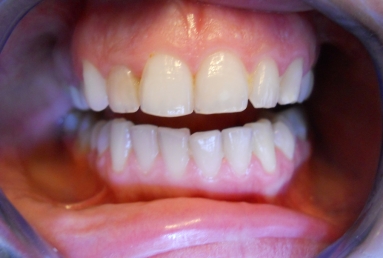

restore the tooth with a very esthetic full ceramic crown

Initial clinical situation: upper lateral incisor with a big composite filling and an old root canal treatment. that caused in time a grey discoloration of the tooth. Internal tooth whitening would not give a good result in this case, because of the composite filling, and also because the whitening is not stable in time. This is why the decision was to restore the tooth with a very esthetic full ceramic crown, which does not change colour in time, at the same time protetcting a non vital tooth against fracture.